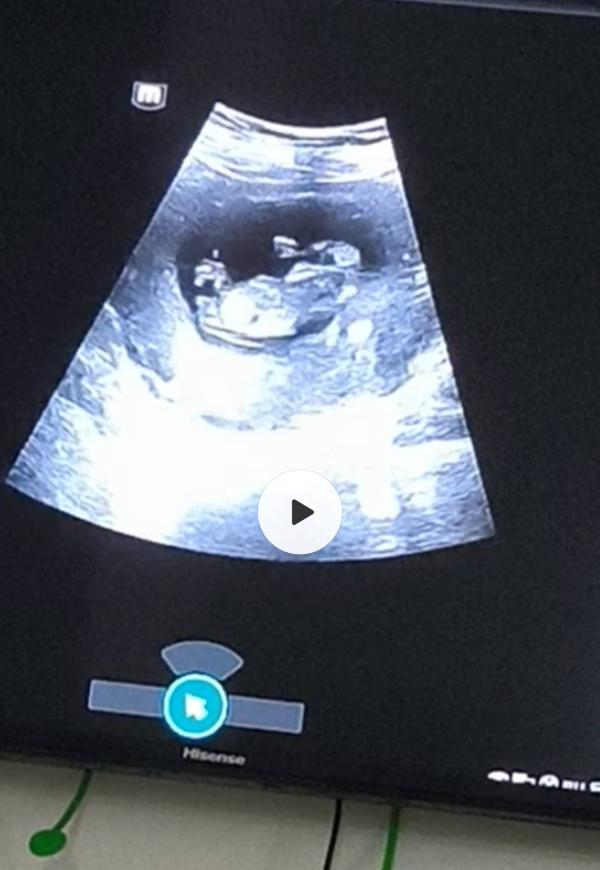

Доброе утро, мамочки) Надежда умирает последней как говорится...Это скрин узи 12 неделя младшего сына, Керималиева редпологала девочку так как половой бугорок был паралельно позвоночнику. Муж из тех редких мужчин которые не требуют наследника ,а хотят принцесс. Он очень обожает сыновей ,но что в первую ,что во вторую очень ждал девочку🥹. И в эту беременность он ждал девочек прям как узнал всё время говорил мои девочки-на руках буду носить.🥰

После УЗИ я конечно сказала предположение врача и говорю кто бы не был как и договаривались после родов делаем вазектомию и всё завершаем. Я больше не хочу рожать ,мне здоровье нужно и этим детям нужно дать достойное образование и жизнь. Он согласился осознавал что пол зависит от него. И сказал что на второе узи пойдем вместе,может ошибка ,с младшим же тоже девочка говорили , вдруг в эту тоже ошиблись. Вот ждёт след.УЗИ

Спасибо🫰🏻 просто на УЗИ я явно увидела стручок смотрящий вверх😅 13 недель по УЗИ вот думаю не ошиблись.